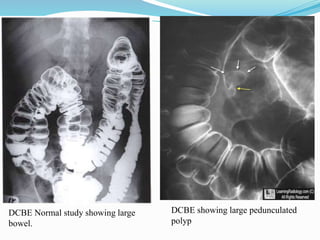

This document discusses colorectal polyps. It defines polyps and describes their types, including neoplastic and non-neoplastic polyps. It discusses adenomatous polyps in depth, noting their malignant potential increases with size over 1cm and villous architecture. Radiological diagnostic methods for polyps including single and double contrast barium enema and CT colonography are explained. The document provides an overview of polyp pathogenesis and genetic syndromes like FAP that increase cancer risk.